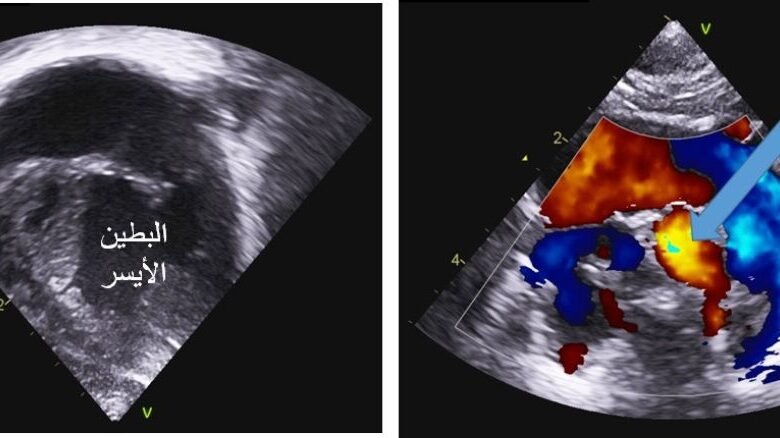

أجرى الفريق الطبي بمركز الأمير سلطان لطب وجراحة القلب بالقصيم في قسم الأطفال قسطره قلبيه لمولود ( وحيد والديه )بوزن 2.9 كجم ، في اليوم 3 من الولادة كان يعاني من رتق كامل للصمام الرؤوي مع صغر شديد في حجم البطين الأيمن ماأدى إلى عدم وصول الدم إلى الرئتين إلا عبر القناة الشريانيه الموصله بين الشريان الابهر والشرايين الرؤويه ، وبعد الفحوصات الطبية قرر الأطباء عمل القسطره قلبية وذلك بوضع دعامة على القناة الشريانيه لضمان وصول الدم إلى الرئتين وتغذية الجسم بالأوكسجين ، واستمر وقت القسطره 30 دقيقه

الجدير ذكره انه تم تشخيص هذه الحاله أثناء الحمل بواسطة الفريق الطبي المتخصص في قسم قلب الاطفال بالمركز ، بعمل تصوير قلب الجنين بالموجات فوق الصوتية وتم متابعة الأم أثناء الحمل وتنسيق موعد ومكان الولادة ، كما تم فحص المولود مباشرة بعد الولاده وتأكيد التشخيص و إعطاءه العلاج المناسب ، كما أجرى المركز خلال الخمسة أشهر الماضية أكثر من 151 قسطرة قلب للأطفال .